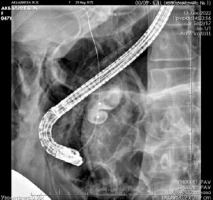

On 13th December 2022: During the endoscopy, the major duodenal papilla (MDP) was not enlarged. The common bile duct (CBD) was catheterized: the proximal part measured up to 1.0 cm in diameter, while the middle and lower thirds were cystically dilated to 2.5–3.0 cm, forming two cavities. Two shadows, measuring 1.1–1.3 cm in diameter, were observed in the lumen of the CBD in the distal part (Figure 3). Endoscopic papillosphincterotomy (EPST) was performed up to 0.7 cm with additional balloon dilation to 1.1 cm. The stones were extracted.

Figure 3

Fistulography during ERCP: visualization of the catheter in the common bile duct (choledochus)